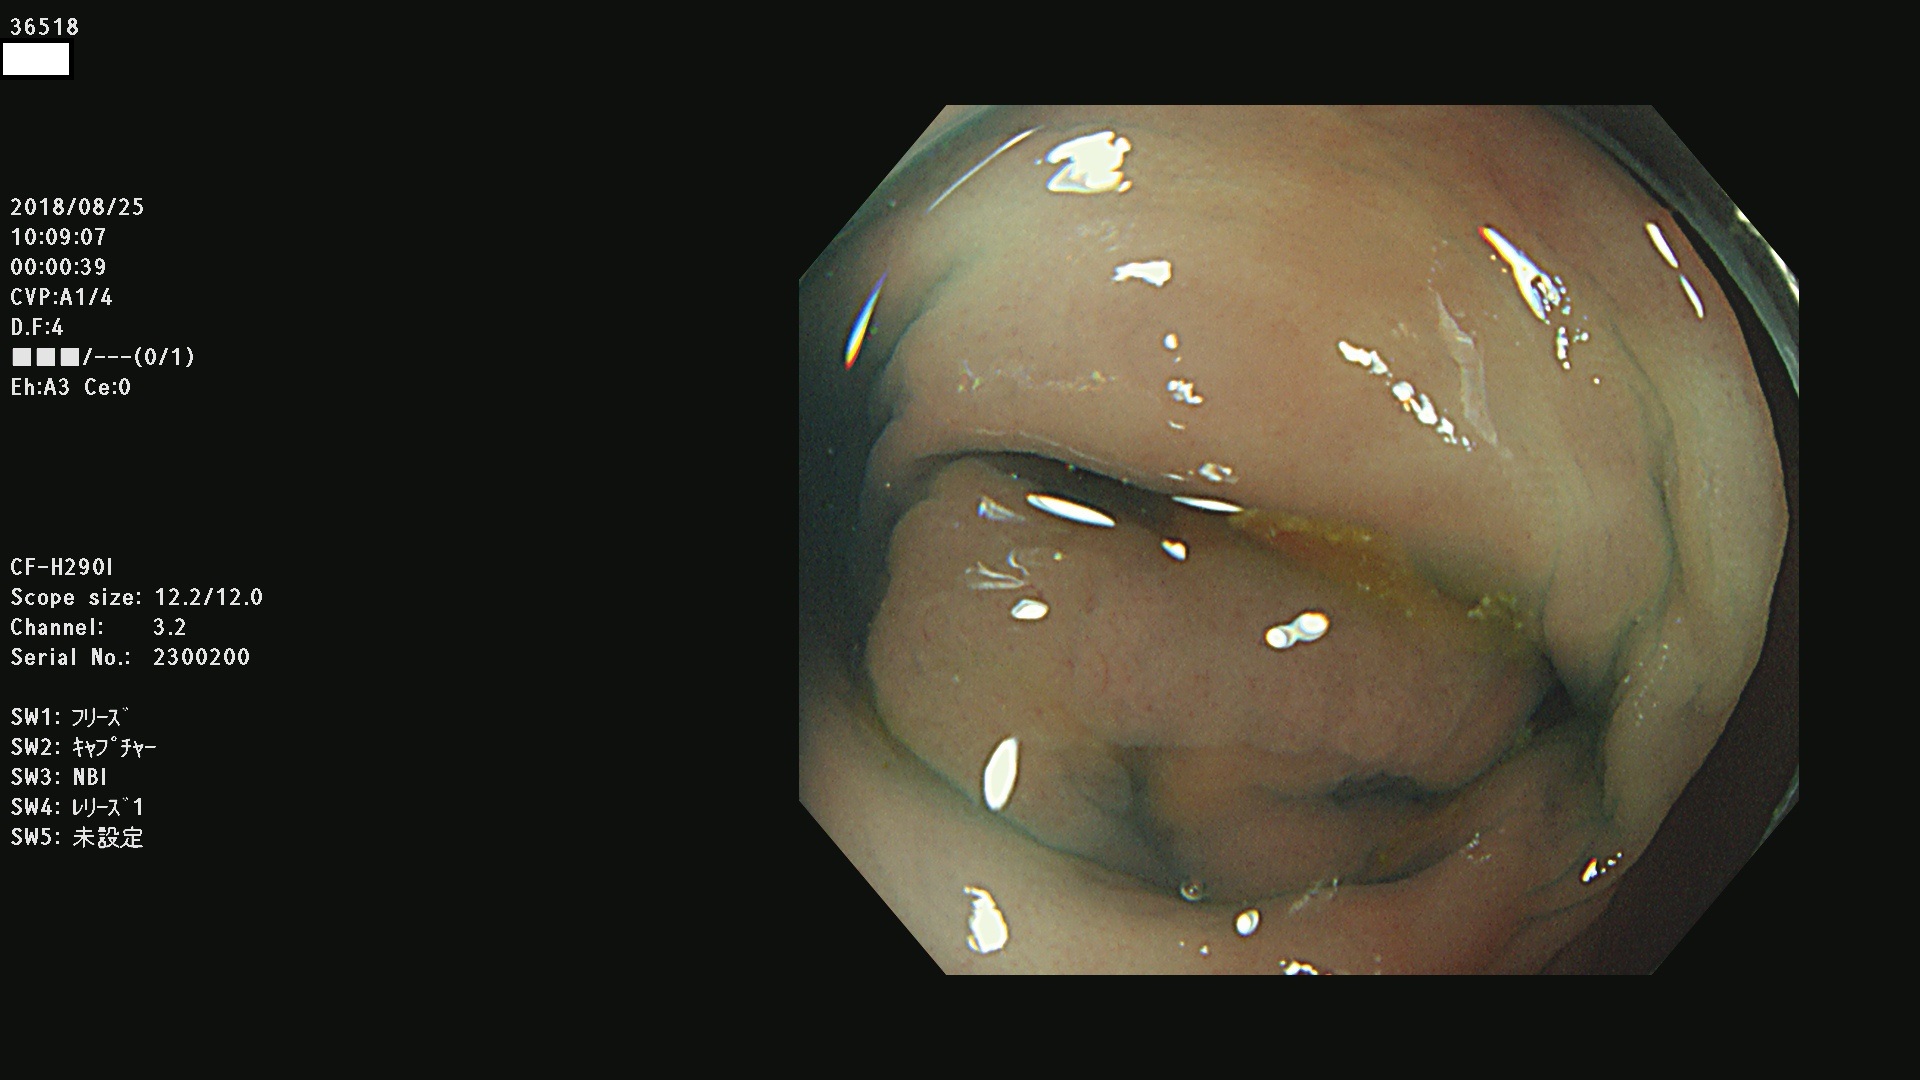

36500 36503 36504 36505 36507(SSAPのみ) 36508 36509 36510 36511 36514 36515 36517 36518 36520 36522(SSAPのみ) 36523 36524 36526 36528 36530 36531 36532 36533 36534 36535 36536 36538 36541 36542 36543 36544 36545 36546 36548 36550 36551 36554 36555 36556 36558 36559 36560 36561 36564 36565 36567 36568 36570 36572 36573 36574 36575 36576 36577 36578 36579 36580 36582 36584 36586 36591 36592 36593 36594 36595 36596 36597 36598

発見困難で危険性の高い平坦型病変(上記100名より抽出)